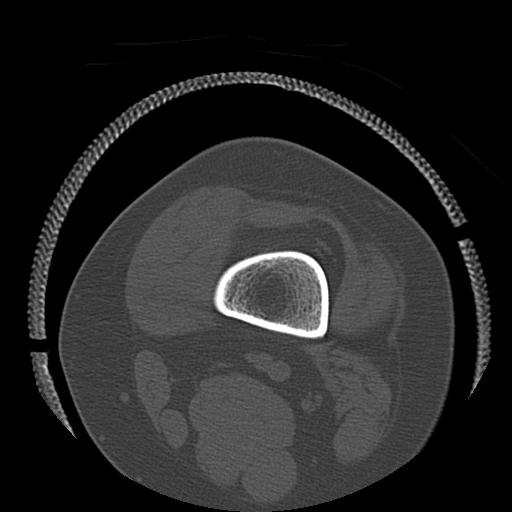

49554 3/13 膝 4R 3/16 4R 1/18 2R 78歳男性 膝蓋骨骨折